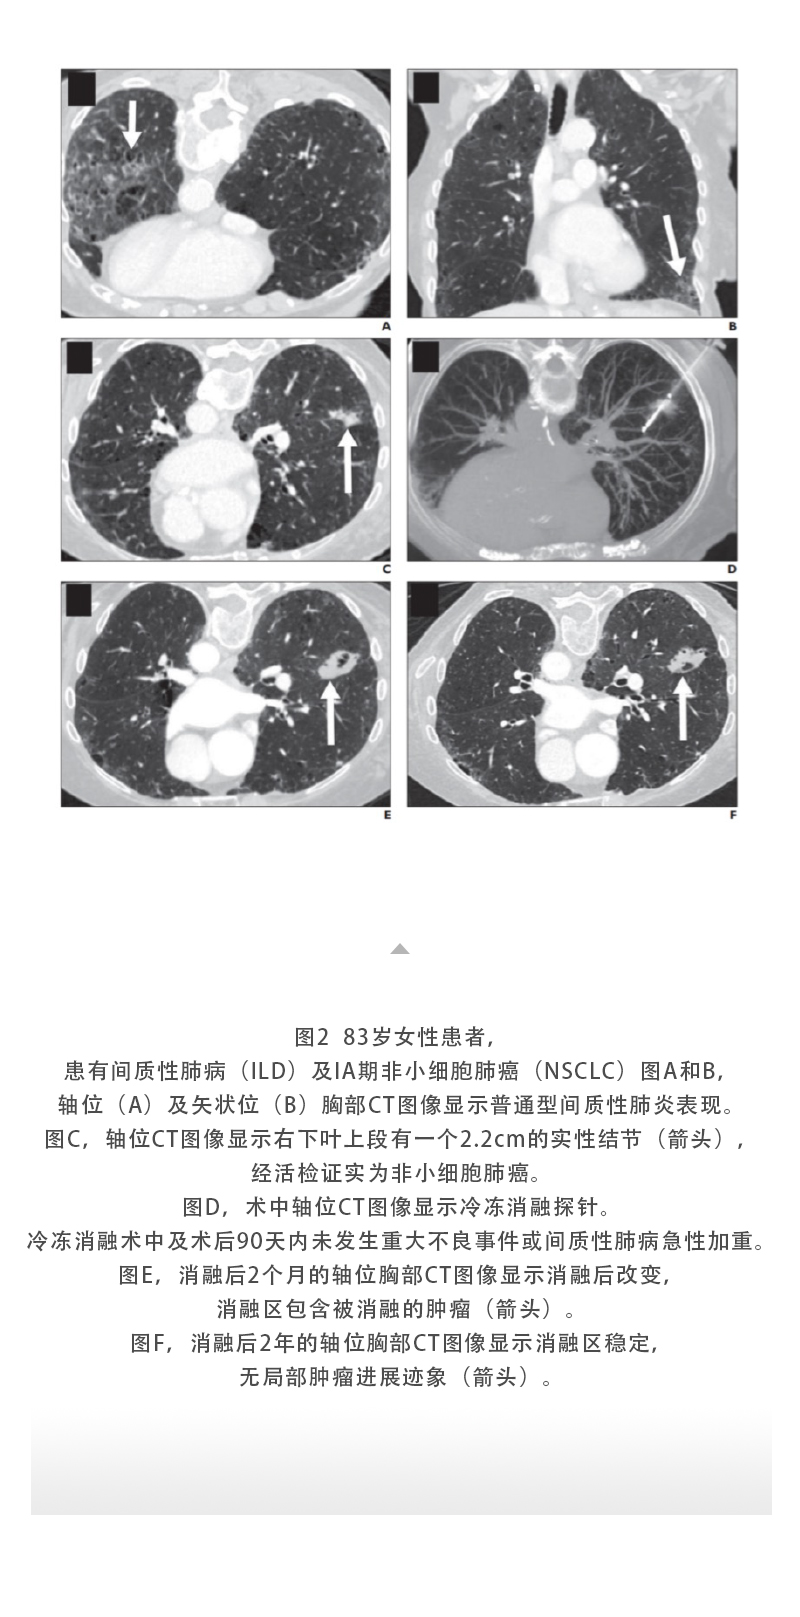

【HYGEA·科研資訊】肺癌冷凍消融

發(fā)布時(shí)間:2025-07-14 | 作者:海杰亞 | 瀏覽次數(shù):301